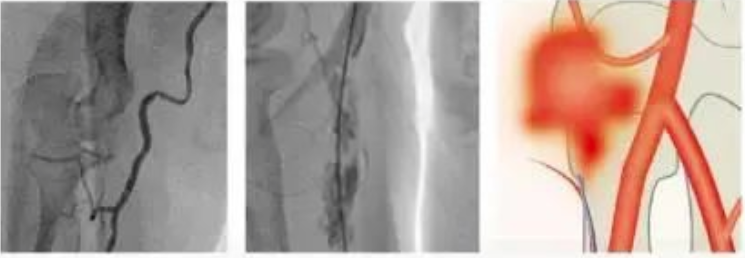

冠状动脉正常,是指冠状动脉解剖结构和起源的完全正以及血管壁光滑无斑块。冠状动脉正常并不代表冠状动脉微管无异常。

1. 冠状动脉异常分为:

(4)冠状动脉病变

2. 从狭窄程度分为:

(1)轻度狭窄:狭窄≤50%,建议药物治疗,控制危险因素

(2)中度狭窄:狭窄 50%~75%,进行功能学评价,包括压力阶差(FFR)测定和负荷心肌试验,也可以考虑血管内超声(IVUS)

(3)重度狭窄:狭窄>75%。建议行PCI或CABG,或药物治疗

(2)扩张性改变:严重者称为冠状动脉瘤,考虑药物抗凝治疗或介人手术治疗